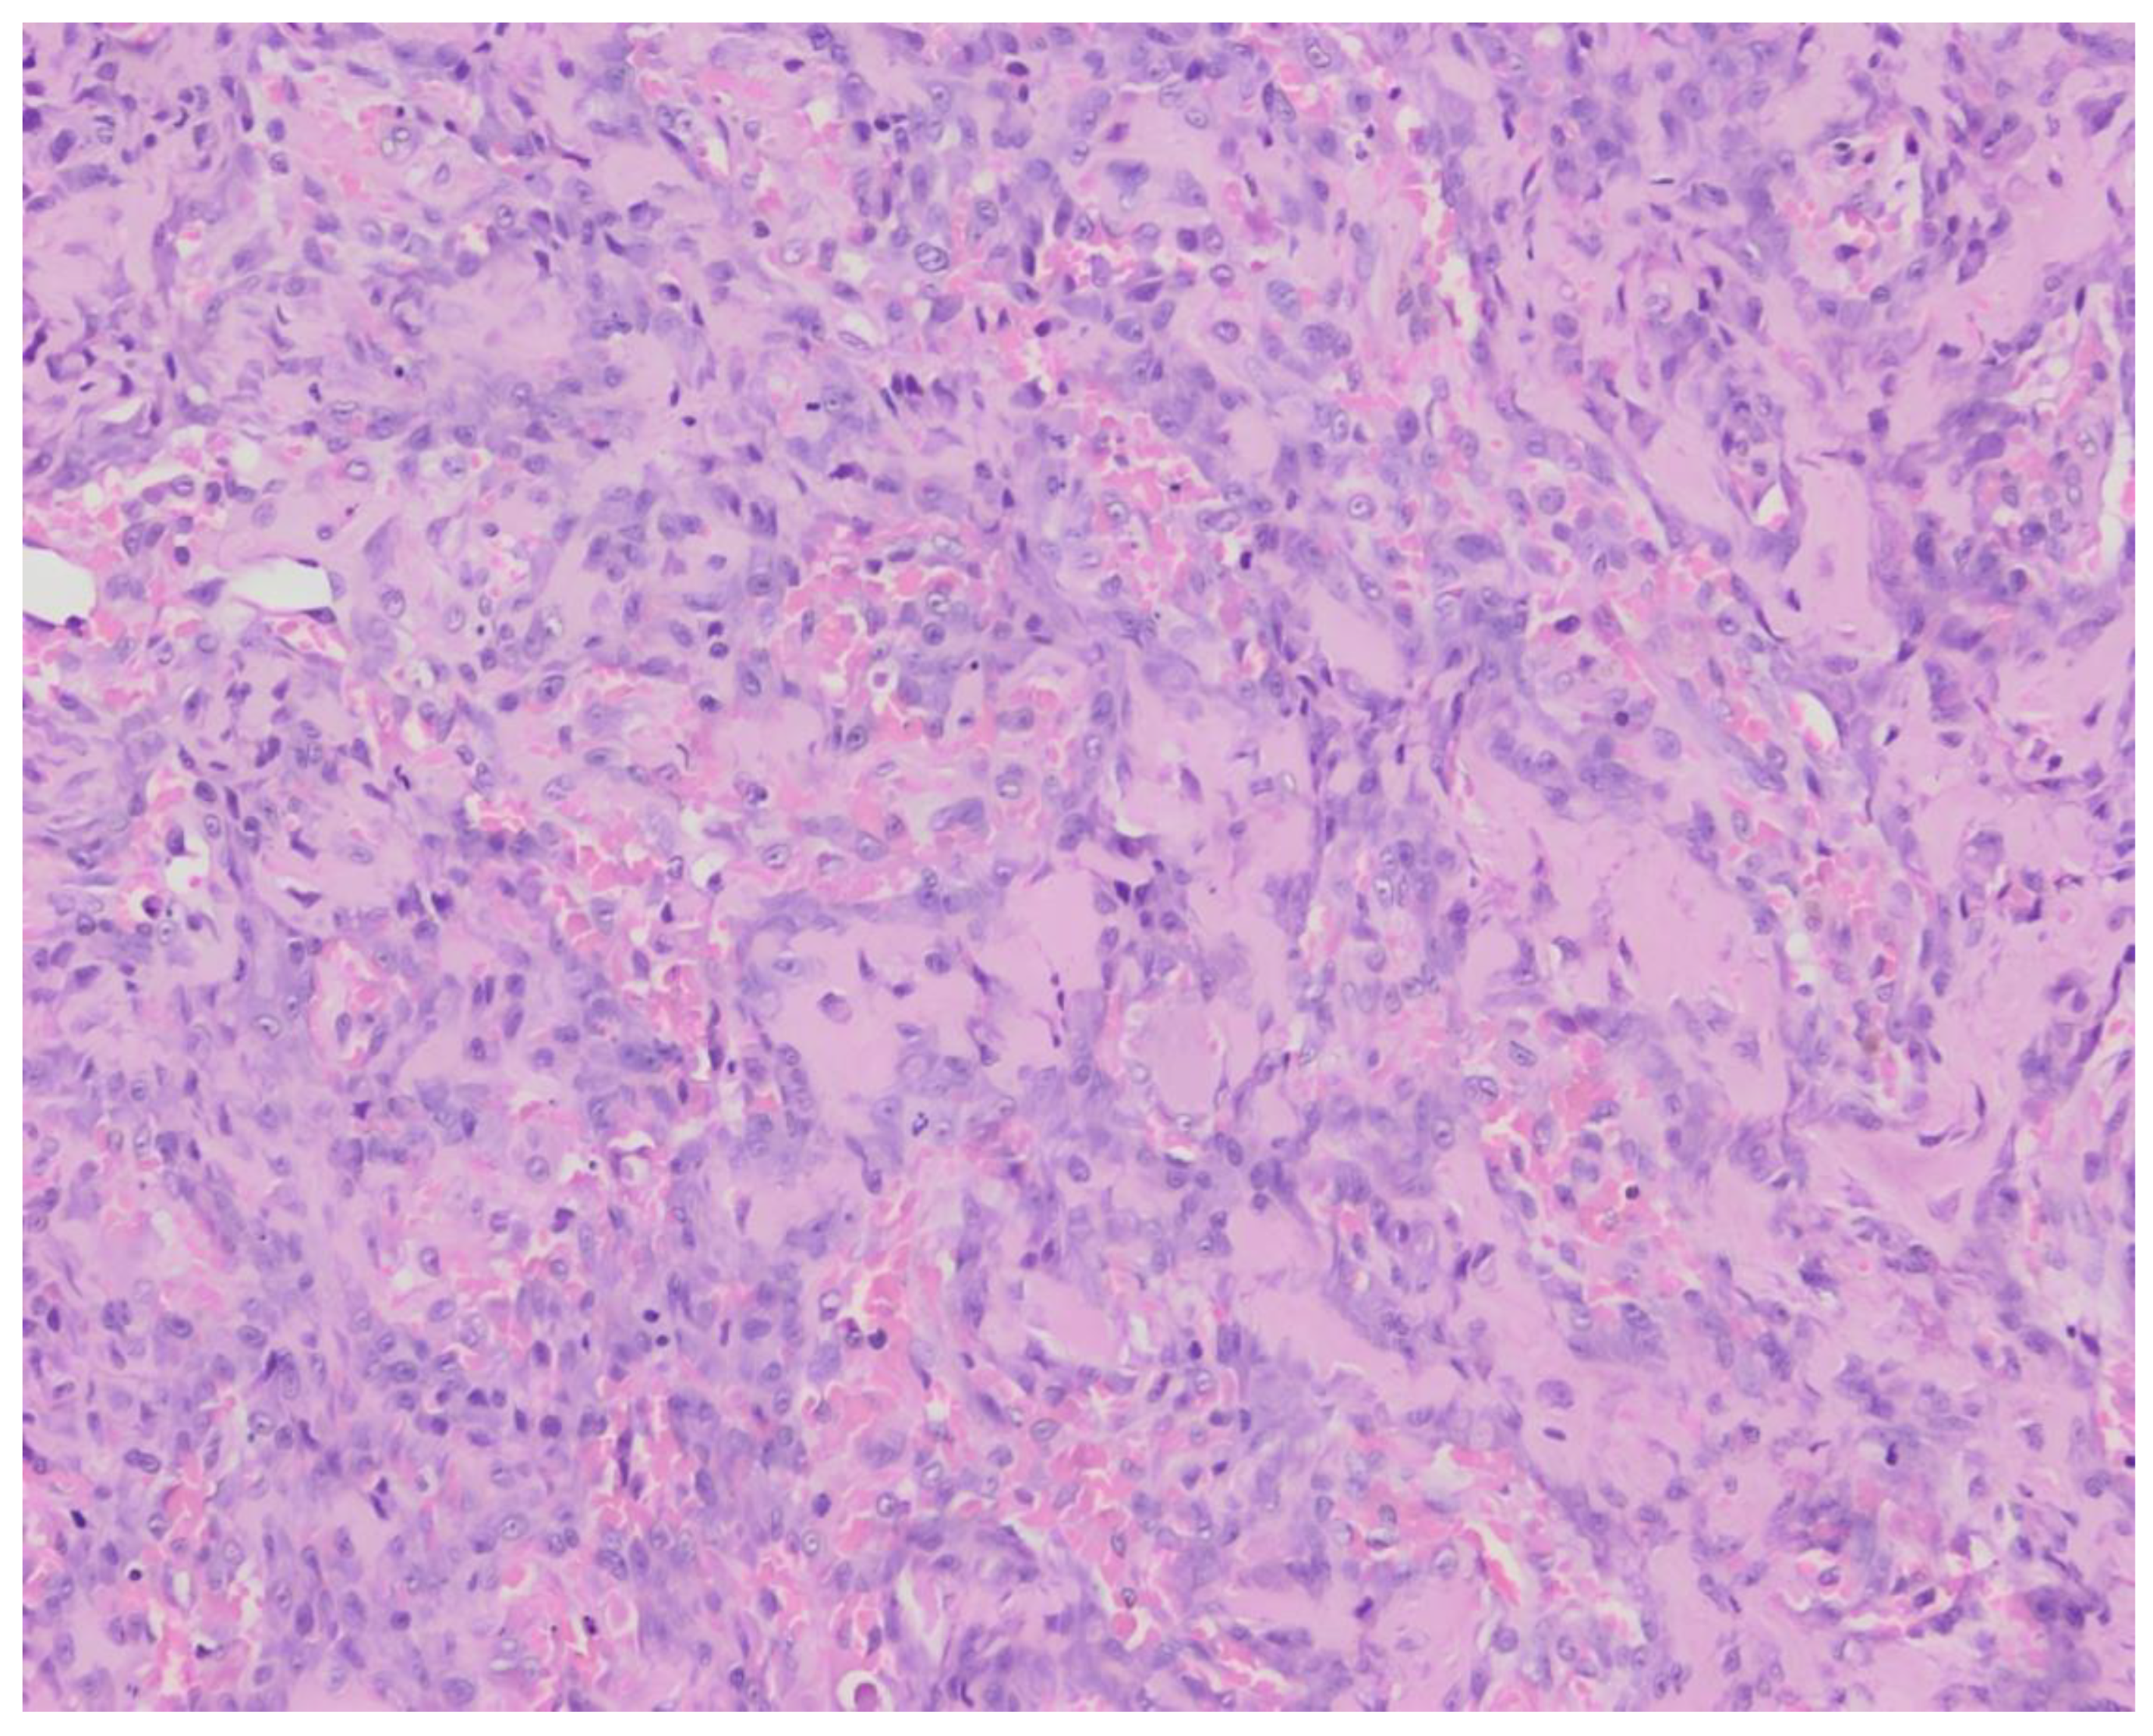

The histopathological examination of surgical biopsies revealed a proliferation of polygonal to plump fusiform mesenchymal cells in clusters with the formation of osteoid in-between the cells (Figure 2). The cells had a round to oval, vesicular nucleus with occasional distinct nucleolus and a small quantity of basophilic cytoplasm. The cells showed moderate anisocytosis and anisokaryosis, with 4 mitoses per 10 high-power fields. Local multinucleated cells were present.These findings were consistent with a vertebral osteosarcoma, osteoblastic productive morphological subtype.

Figure 2. Histopathology of surgical biopsies of case 1. Hematoxylin and eosin stain, 200×. Polygonal to fusiform tumor cells surrounding eosinophilic, relatively abundant osteoid.